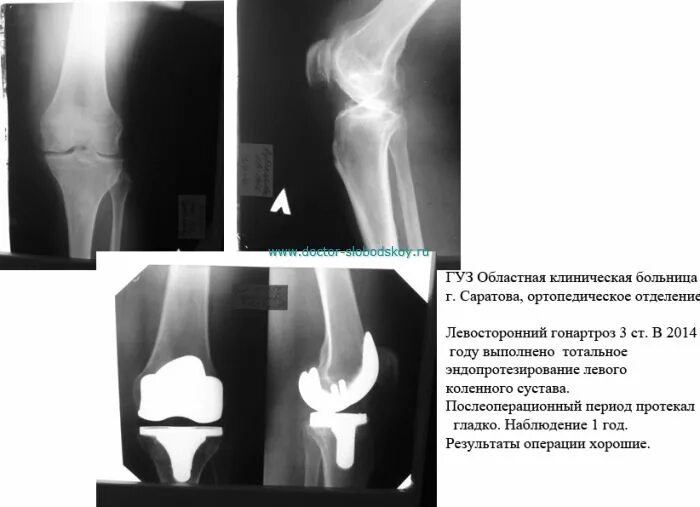

Гонартроз мрт